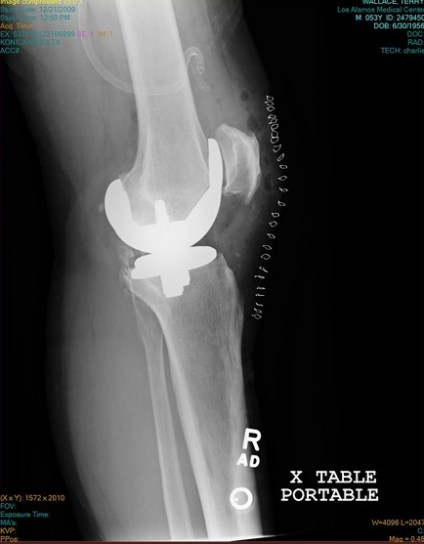

Xray of my right knee shortly after surgery. The “picket fence” on the right side of the image are the staples to close the incision. The replacement includes implants both on the femur and the tibia bones. The knee cap is also reshaped and spurs and growths were removed.